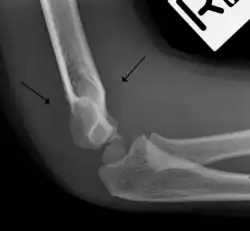

The fat pad sign, also known as the sail sign, is a potential finding on elbow radiography which suggests a fracture of one or more bones at the elbow. It may indicate an occult fracture that is not directly visible. Its name derives from the fact that it has the shape of a spinnaker (sail).[1] It is caused by displacement of the fat pad around the elbow joint. Both anterior and posterior fat pad signs exist, and both can be found on the same X-ray.

In addition to fracture, any process resulting in an elbow joint effusion may also demonstrate an abnormal fat pad sign. Increased intracapsular fluid is also seen in several conditions other than fracture and this produces the abnormal fat pad sign. (toxic synovitis, septic arthritis, Juvenile Rheumatoid Arthritis, osteomyelitis of the distal humeral physis and secondary septic joint). In these instances, history and clinical examination in addition laboratory results (WBC, ESR, CRP) will guide the provider in determining whether to treat the condition as an occult fracture or continue workup for other pathology.

The posterior fat pad is normally pressed in the olecranon fossa by the triceps tendon, and hence invisible on lateral radiograph of the elbow.[3] When there is a fracture of the distal humerus, or other pathology involving the elbow joint, inflammation develops around the synovial membrane forcing the fat pad out of its normal physiologic resting place. This is visible as the "posterior fat pad sign" and is often the only visible marker of a fracture, particularly in the pediatrics population.